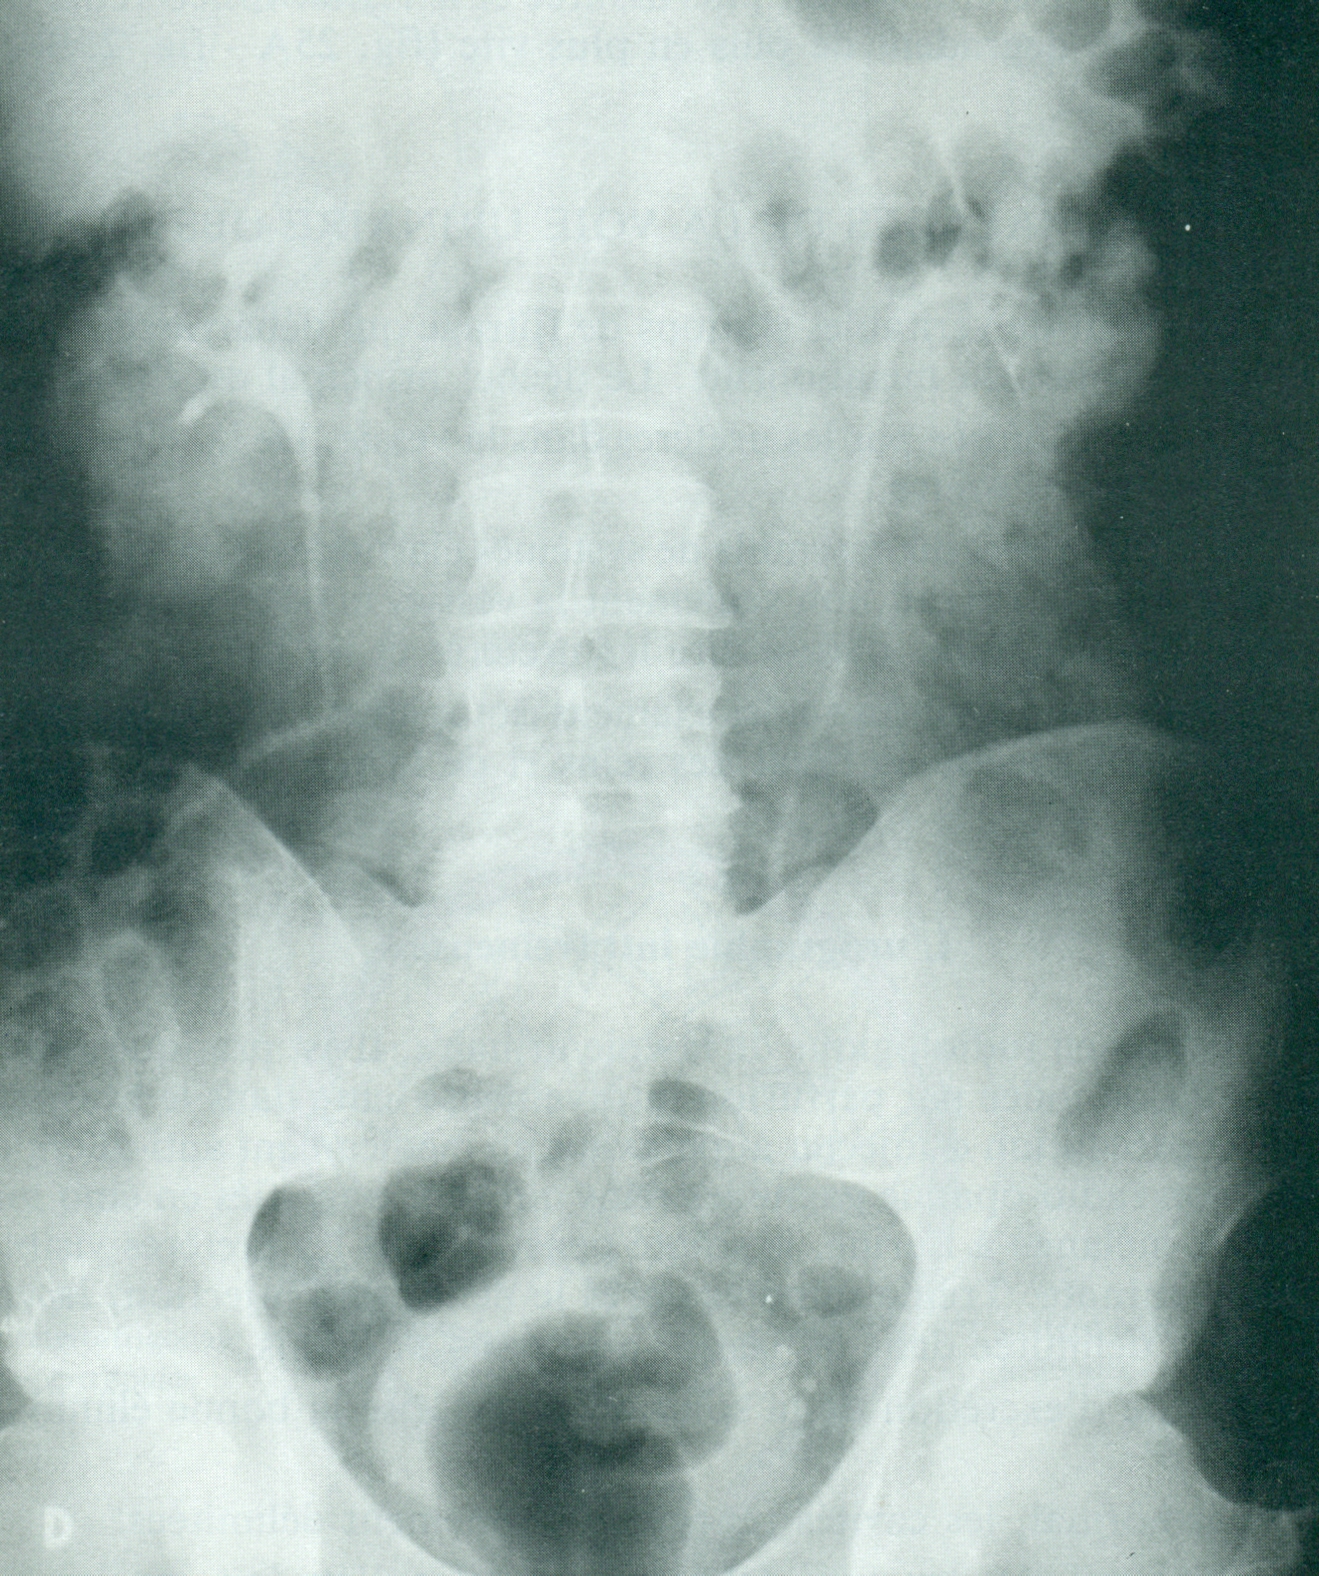

D.

Néphrogramme isotopique anormal. Les courbes démontrent une

élimination lente des deux reins.